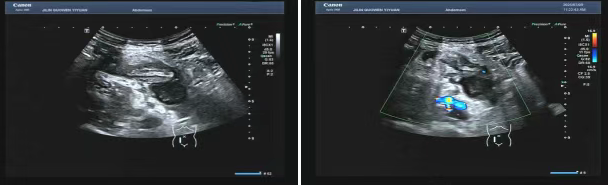

80 歲的張爺爺(化名)因前列腺增生前往國文醫(yī)院就診,泌尿外科為其開具了泌尿系超聲檢查。超聲科醫(yī)生在檢查過程中,憑借敏銳的觀察力,發(fā)現(xiàn)患者右下腹有異常混合回聲包塊。醫(yī)生沒有放過這一異常,立即展開進一步探查,結(jié)果顯示包塊內(nèi)疑似有闌尾結(jié)構(gòu),且周圍組織存在粘連,還伴有液性暗區(qū)??紤]到老年患者病情往往較為隱匿,癥狀也不典型,醫(yī)生第一時間與臨床醫(yī)生溝通,建議進行緊急處理。隨后,經(jīng)過臨床醫(yī)生詳細檢查,患者迅速辦理住院并接受手術(shù),術(shù)后病理檢查結(jié)果確診為 “闌尾壞疽伴穿孔合并膿腫形成”。

主治醫(yī)生介紹,老年人患闌尾炎時,癥狀常常不典型,很容易被誤診為腸胃炎或其他疾病。張爺爺僅表現(xiàn)出輕微腹脹的癥狀。倘若不是超聲檢查時意外發(fā)現(xiàn),極有可能延誤治療,進而引發(fā)感染性休克,甚至危及生命。超聲檢查在這類急腹癥的篩查中,發(fā)揮了至關(guān)重要的作用。